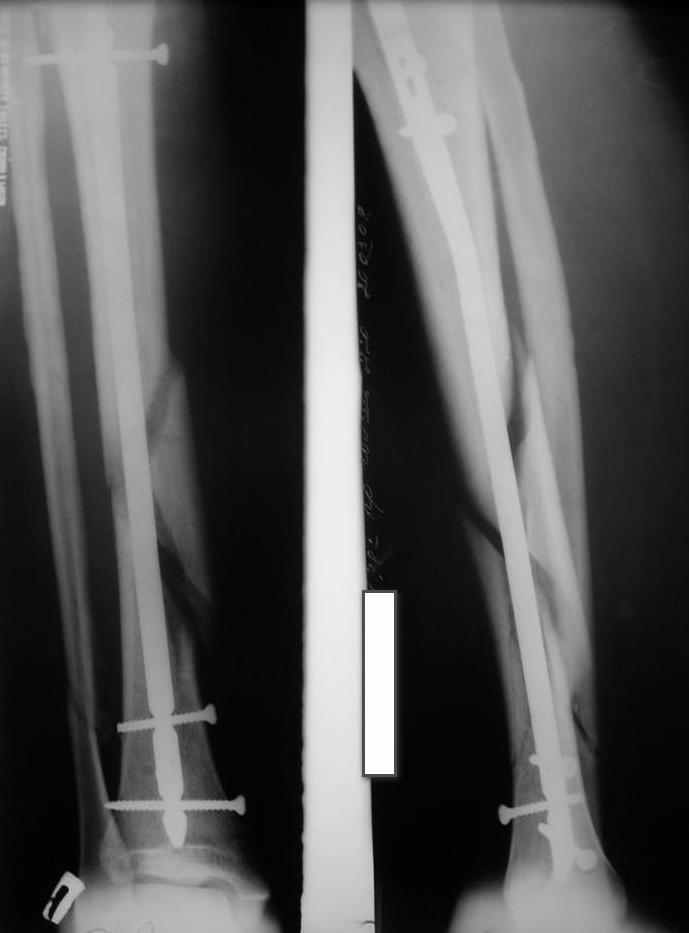

У нас был молодой пациент М.(26лет), травма 25 января 2009г, катался на лыжах и получил травму. Поступил к нам в отделение в экстренном порядке. При обследованиии выявлен закрытый винтоообразный оскольчатый перелом правой большеберцовой кости и косой перелом малоберцовой кости на границе средней и нижней трети. Выполнен интрамедуллярный блокируемый синтез большеберцовой кости, оси и длина конечности восстановлена. После операции пациент ходил с полной нагрузкой. Через 3 месяца на контрольных рентгенограммах сращения нет, динамизации не выполняли, так как оскольчатый перелом.(снимки в динамике прилагаются). Посоветуйте, что в данном случае делать наиболее целесообразно?

Какие-то признаки консолидации все же угадываются, так что при остутствии клинических жалоб мы бы подождали с динамизацией еще 6-8 недель.

мы бы подождали с динамизацией еще 6-8 недель

Отсутствие уверенных признаков сращения неделям к 8 - надо динамизировать. Тут уже 3,5 мес., есть щель из-за смещения по длине. Дальнейшее консервирование ситуации тут не решает никаких проблем, а вот создать их может. Динамизация с нагрузкой и диастаз уменьшит, и репаративный процесс "освежит".